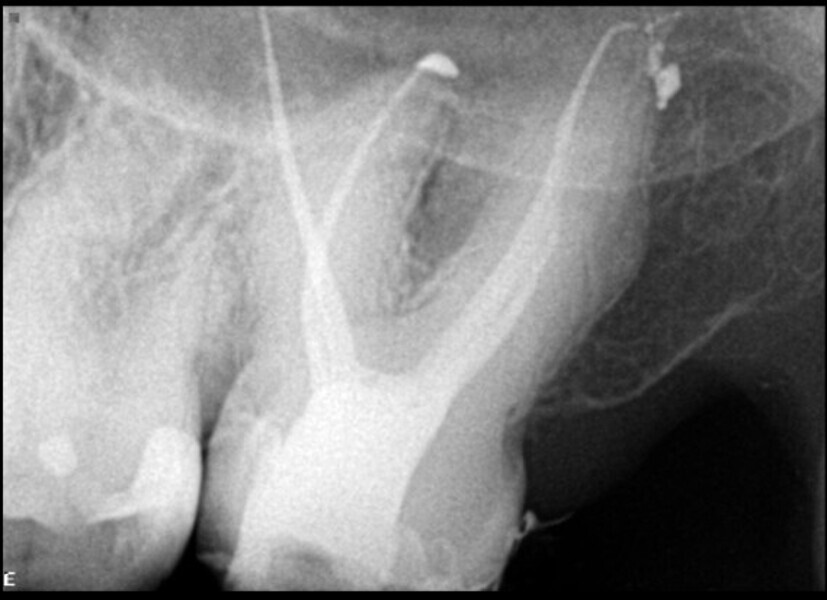

I asked for an i-CAT scan to be taken in order to better understand what was going on. Studying the horizontal view of the 3D image, the level of calcification in the pulp chamber compared with the pulp chamber of the first molar could be seen clearly (Fig. 2).

Fig. 2: Horizontal cross section taken from the i-CAT scan (DEXIS) showing total calcification of the root canal orifice at the level of the cemento-enamel junction, in comparison with the first molar.